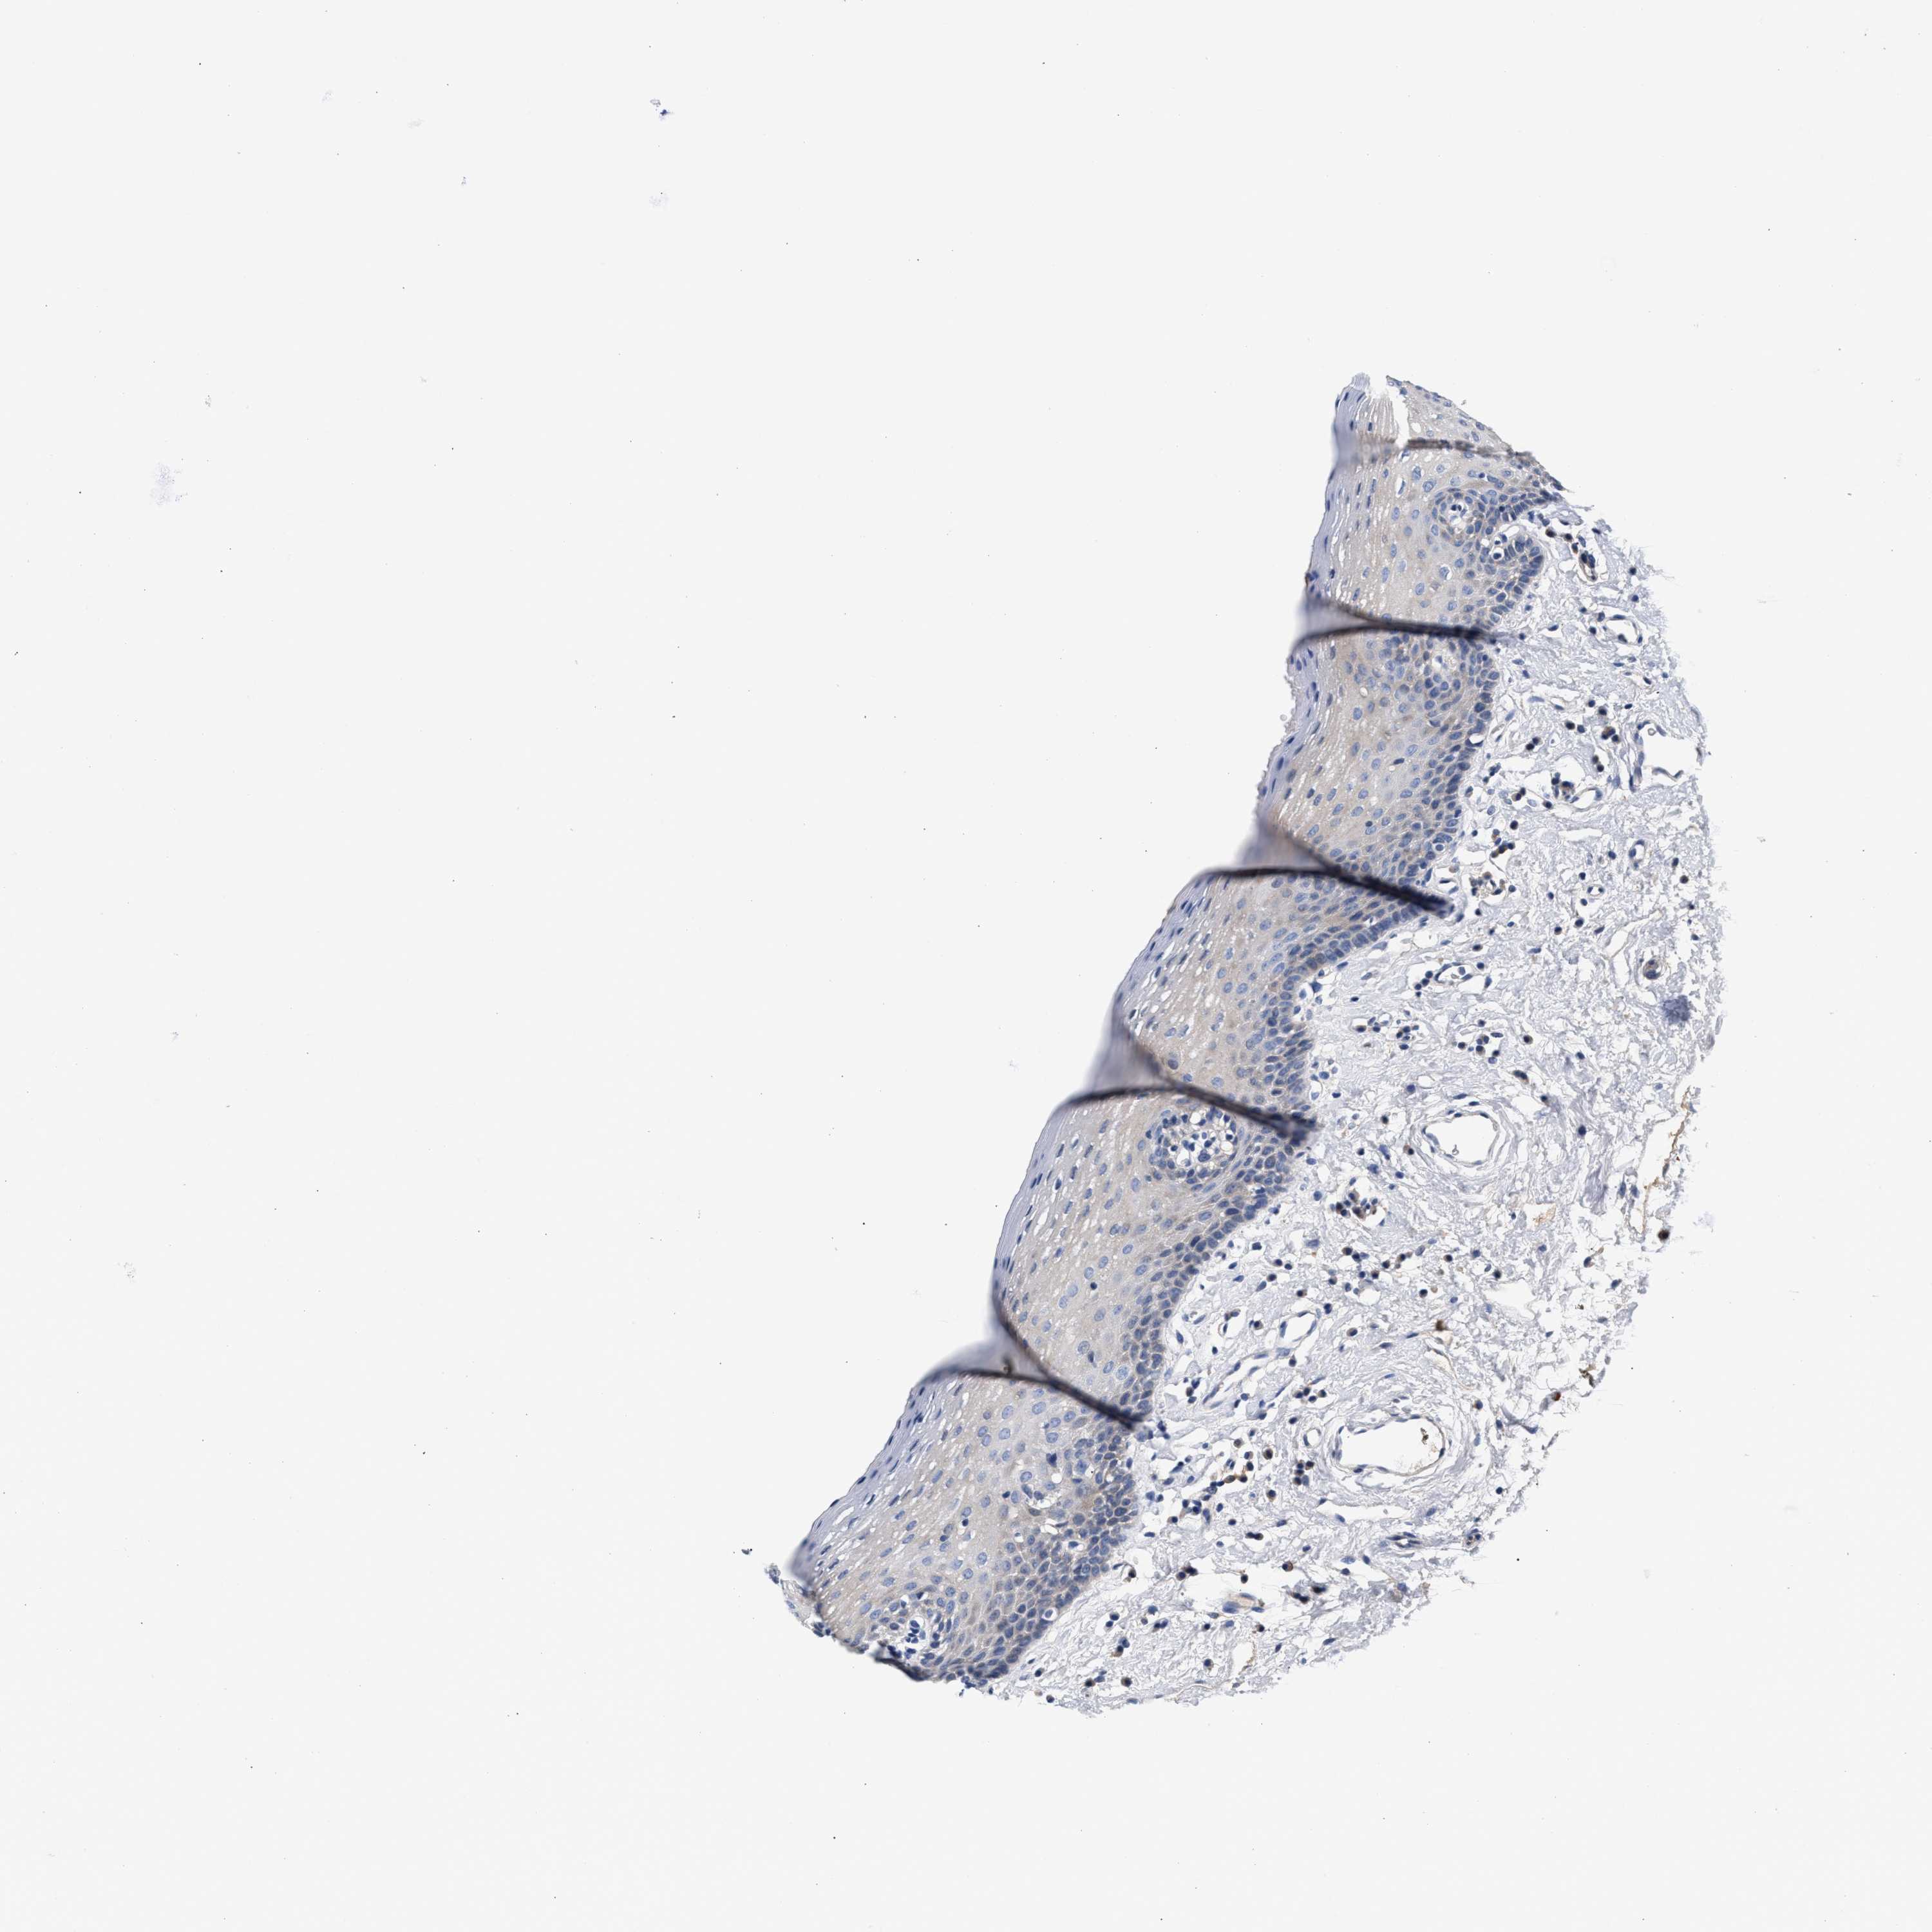

TISSUE PRIMARY DATA ORAL MUCOSA Show tissue menu

ORAL MUCOSA - Antibody stainingi

Antibody staining in the annotated cell types in the current human tissue is reported as not detected, low, medium, or high, based on conventional immunohistochemistry profiling in selected tissues. This score is based on the combination of the staining intensity and fraction of stained cells.

Each image is clickable and will lead to virtual microscopy that enables deeper exploration of all samples and also displays staining intensity scores, fraction scores and subcellular localization as well as patient and tissue information for each sample.

Antibody HPA021165Antibody HPA021753Antibody HPA021760

Squamous epithelial cells Not detectedLowNot detected